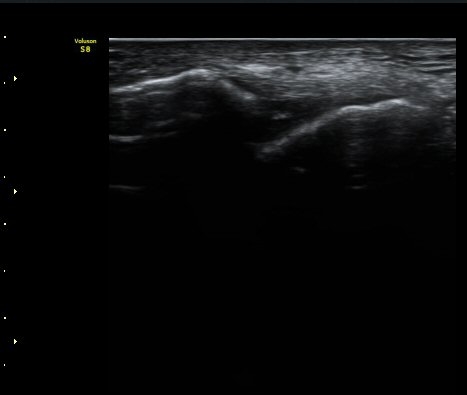

¹ß¸ñ°üÀý ¾Õ Á¾´Ü¸é°Ë»ç¿¡¼­ ¼Ò·®ÀÇ ¼ö¾×Àú·ù°¡ °üÂûµÈ´Ù(±×¸² 1, 2).